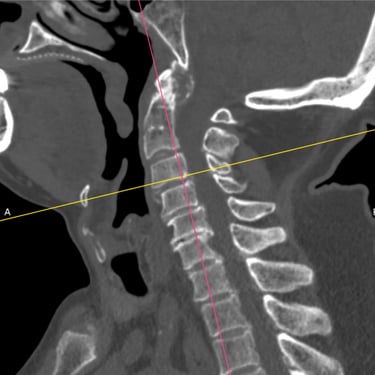

🧠Hernia Cervical con Mielopatía: ACDF con Cage y Placa asistida con Monitoreo Neurofisiológico.

La hernia cervical con mielopatía genera compresión medular y deterioro neurológico. La ACDF con cage y placa, asistida con monitoreo neurofisiológico intraoperatorio, permite una descompresión segura, estabilización cervical y mayor protección neurológica, favoreciendo una recuperación funcional progresiva.